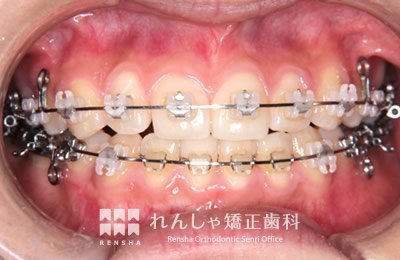

永久歯列はほぼ完成してしますが、歯列を側方だけでなく後方へも拡大し、埋まっていた右上奥歯を引っ張り出しています。

| 主訴 | 埋まったままでてこない歯がある |

|---|---|

| 診断名 | Angle Class II 小臼歯の埋伏と叢生を伴う上顎前突 |

| 初診時年齢 | 13歳5か月 |

| 装置名 | マルチブラケット装置 |

| 抜歯非抜歯 | 非抜歯 |

| 治療期間 | 2年3か月 |

| 費用の目安 | 約82万円+消費税(検査料金、都度の処置費用等も合わせた総額) |

| リスク副作用 | 歯の移動に伴う軽微な歯根吸収、歯槽骨吸収、歯肉退縮(本症例では軽度の歯根吸収を認めた)、矯正器具装着中のカリエスリスク増大(本症例ではカリエス発生無し) |